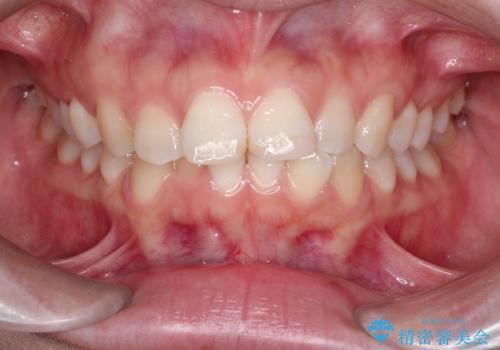

突き出た前歯を下げて理想的な横顔に。上下左右4番抜歯による審美ワイヤー矯正